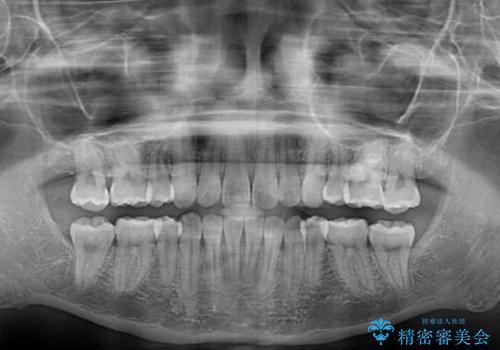

- 上下の八重歯や乱杭歯を気にして来院され患者様です。

スペースを確保するため、上下左右の第一小臼歯を抜歯し、ワイヤー装置に矯正することとしました。

その後スペースを閉じるために時間を要しましたが、満足のいく仕上がりとなりました。